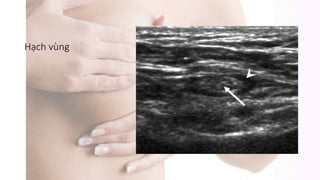

Siêu âm

Hạch vùng